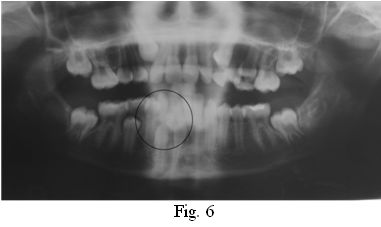

Al examen radiográfico se observa una lesión radiopaca, compuesta por varios dentículos, rodeada de una zona radiolúcida bien delimitada. Se diagnostica la presencia de un Odontoma Compuesto que representa una traba de erupción para los órganos dentarios 4.2 y 4.3 (Figs. 6 y 7).

Los odontomas compuestos son los tumores odontogénicos más frecuentes, relacionados con dientes permanentes retenidos. En este caso clínico, se presenta un odontoma compuesto de alrededor de 10 mm de diámetro, asintomático, en el sector anterior del maxilar inferior. Fue un hallazgo radiográfico indagando sobre la etiología de la ausencia de algunas piezas permanentes y el desplazamiento de otras, asociado a la persistencia de un diente caduco (8.3), lo que coincide con lo descrito por varios autores (7, 8, 11, 12, 17). En concordancia con la bibliografía consultada, los controles periódicos clínicos y radiográficos realizados a la paciente luego de la eliminación quirúrgica del odontoma, no muestran signos de recidiva (3, 12, 23, 26).